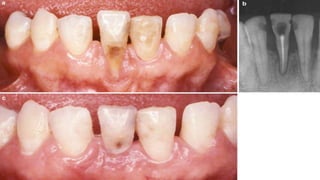

• #13 Class I gingival recessions– Baseline (a), recession depth of 3 mm (b), planning the papillary incisions (c), horizontal incisions performed as reported by Zucchelli and de Sanctis (d)

• #14 flap raised without releasing incisions (e), papillae de- epithelialization (f), flap coronally advanced and sutured as much as possible (with no tension) (g), 14-day follow-up (h), 4-month follow-up (i)